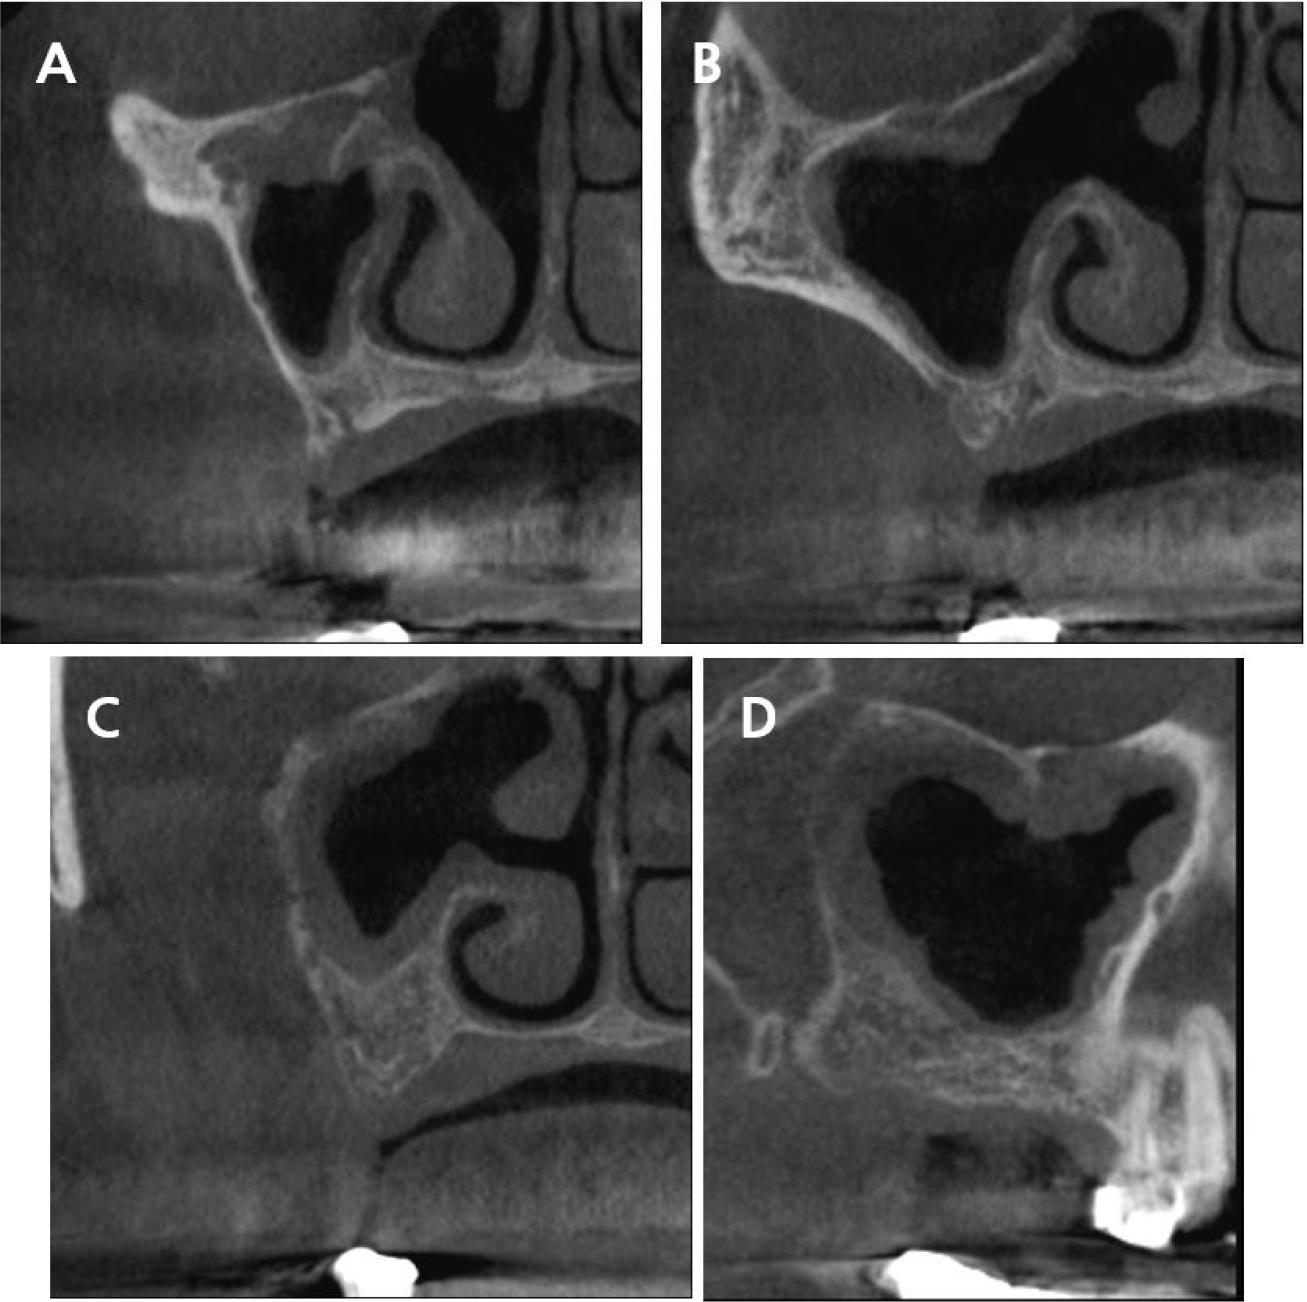

After several months of follow-up, the patient was called to place implants in the posterior maxilla in June 2021. CBCT was performed and complete tumor removal was confirmed (Fig. 2). Furthermore, dissection of part of the sinonasal structures and generalized mucosal thickening along the sinus wall were observed. Since the neoplasm was removed by ESS and not the Caldwell–Luc method, the otolaryngology department observed that dental surgery could be performed without any specific precautions. However, regular check-ups were necessary, and surgical re-entry would be required if the inverted papilloma recurred.

Implant placement with sinus floor elevation was conducted approximately 6 months after ESS. Because of the mucosal thickening observed after the otolaryngologic surgery and possibility of inverted papilloma recurrence, two implants instead of three were placed in the maxillary second premolar and second molar sites, respectively, to simplify and minimize the dental surgery. Implant placement in the first molar region was omitted, because the residual bone height was <4 mm and would need a lateral window technique with graft materials for sinus floor elevation. The osteotome technique without grafting materials was used, and short implants of length 8.5 mm were placed in the second premolar and second molar areas (TS III 4.5 × 8.5 mm and 5.0 × 8.5 mm; OSSTEM, Seoul, Korea). Both implants were placed with sufficient initial stability, and the patient did not report any postoperative discomfort.